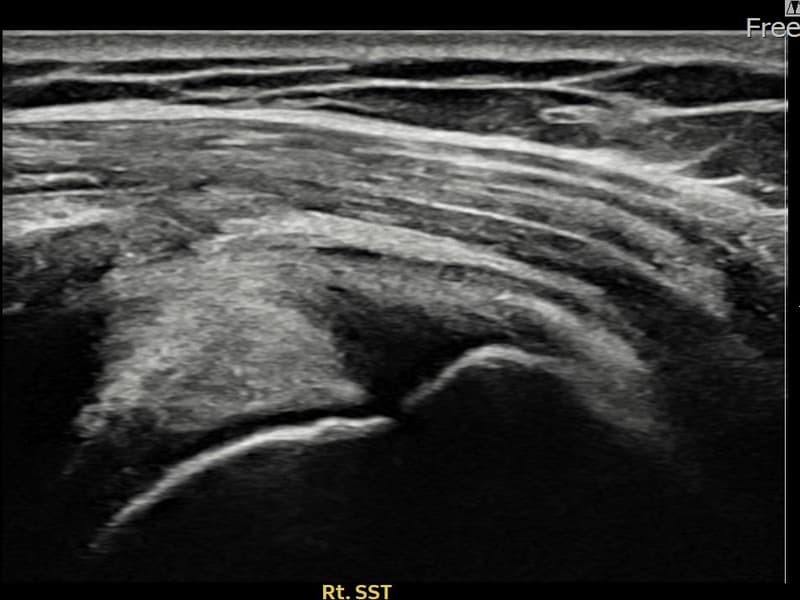

Before

시술 전 초음파 측정 결과 파열 크기는 8mm × 4mm (힘줄 두께의 약 35% 결손)로 확인되었습니다. 시술 전 초음파에서 우측 극상근건 점액낭면측의 에코 단절과 힘줄 내 결손 소견이 확인되었습니다. 시술 후 초음파에서 결손 부위에 재생 조직이 채워지고 힘줄 두께가 정상 범위로 회복된 것이 관찰되었습니다.

60대 초반 여성 환자분으로, 우측 어깨 외측 통증이 지속되어 내원하셨습니다. 팔을 머리 위로 올리거나 뒤로 젖히는 동작이 불편하고, 팔꿈치를 붙인 채 팔을 바깥쪽으로 돌릴 때 통증이 심하다고 하셨습니다. 정밀 초음파 검사에서 우측 극상근건 점액낭면측 부분파열이 확인되었으며, 초음파 유도 하 축소봉합술을 시행하였습니다. 시술 후 보조기를 착용하며 재활 운동을 단계적으로 진행하였고, 시술 11주 후 추적 초음파에서 파열 부위 연속성이 회복되어 정상 생활에 복귀하셨습니다.